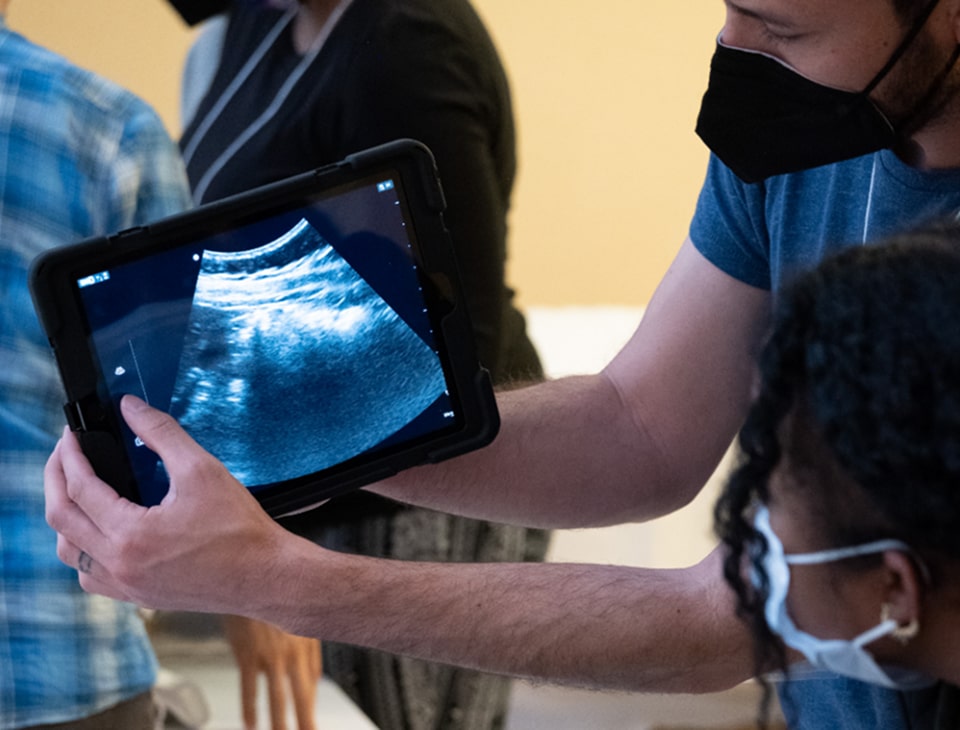

Point-of-Care Ultrasound (POCUS) is transforming obstetric care, helping clinicians assess pregnancies with speed and confidence. From confirming pregnancy to evaluating complications, POCUS supports safer, more informed decisions. GUSI’s Obstetrics POCUS training prepares you to use ultrasound across every stage of pregnancy.

In today’s obstetric care, providers need tools that offer real-time, accurate information to support safer pregnancy management. POCUS gives obstetric professionals immediate insights to confirm fetal viability, detect complications early, and guide urgent interventions. Whether in routine checkups or emergency situations, POCUS is helping obstetric teams deliver faster, more confident, and patient-centered care.

Real-World POCUS Use Cases in Obstetrics

Early Pregnancy Evaluation

POCUS helps confirm intrauterine pregnancy, assess fetal heartbeat, and detect ectopic pregnancies, providing critical information during early visits.

Bedside Assessment of Complications

POCUS supports immediate evaluation of bleeding, fetal position, and amniotic fluid levels at the bedside, guiding timely interventions.

Emergency Triage in Low-Resource Settings

POCUS empowers obstetric teams to make fast triage decisions in emergencies or rural clinics, supporting safer outcomes for mothers and babies.